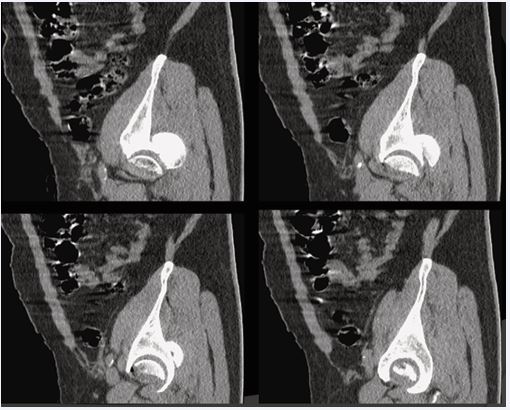

Figure 3 Pre-operative hip CT (sagittal reconstructions) Sagittal reconstructions highlighting intra-articular fragments and femoral head involvement.

Discussion-Early HO Surveillance and Prophylaxis